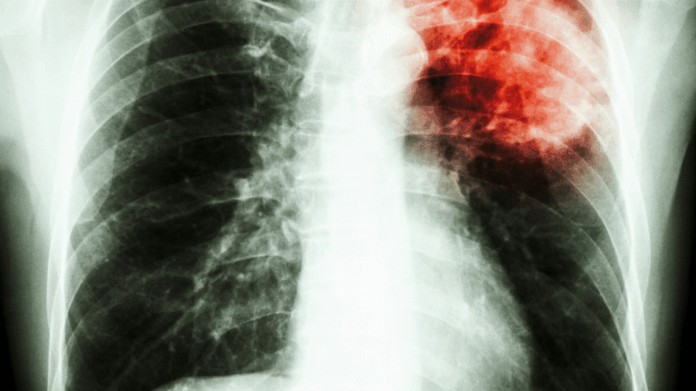

La Journée mondiale de lutte contre la tuberculose, célébrée chaque année le 24 mars, commémore la découverte de la bactérie par le Dr Robert Koch en 1882. En 2026, cette journée porte un message d’espoir avec le thème : « Oui ! Nous pouvons mettre fin à la tuberculose : menée par les pays, portée par les populations. » L’Organisation mondiale de la Santé profite de cette occasion pour exhorter les pays à accélérer le déploiement de nouveaux outils technologiques capables de transformer radicalement la lutte contre cette épidémie.